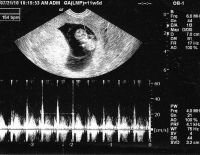

Siêu âm tim thai và những thông tin mẹ bầu cần nằm lòng

Siêu âm tim thai là phương pháp được áp dụng rất phổ biến trong y học giúp chẩn đoán tim bẩm sinh ở giai đoạn tiền sản. Vậy cụ thể những trường hợp nào cần thực hiện siêu âm, nên tiến hành siêu âm khi...